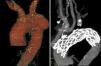

Caso 1. Varón de 58 años de edad con antecedentes de tabaquismo, hipertensión, diabetes, hipercolesterolemia, obesidad, enfermedad arterial periférica y cardiopatía isquémica que precisó implantación de stent coronario en 2009 y 2010. Ingresa en nuestro centro por disfonía, tos y dolor centrotorácico de 2 semanas de evolución. En radiografía de tórax se aprecia ensanchamiento mediastínico. Realizándose angio-TAC, se diagnostica de aneurisma sacular de 7×5,5×5cm, próximo a la salida de la carótida común izquierda (< 8mm) (fig. 1A).

El tiempo de seguimiento ha sido de año y medio y de un año respectivamente. Se ha realizado TAC de control al mes, a los 3 meses y al año de la intervención. Se aprecia permeabilidad de los injertos extraanatómicos, correcta posición de la endoprótesis, ausencia de fugas y exclusión del aneurisma del cayado aórtico (fig. 1B).